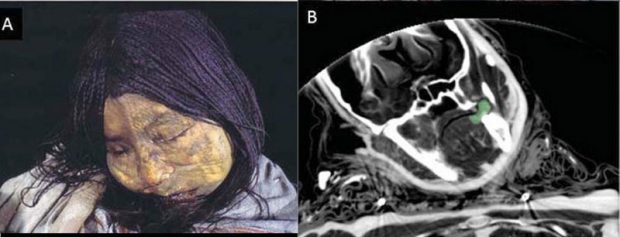

کشف دختر مومیایی ۵۰۰ ساله در کوههای آتشفشانی «لو لای لاکو » آرژانتین این روزها به عنوان خبری جالب و شنیدنی در محافل علمی نه تنها برای محققین موضوع جالبی بوده بلکه در شبکه های اجتماعی نیز مورد توجه عموم قرار گرفته است. این دختر مومیایی و منجمد ۱۴ الی ۱۵ ساله سن داشته که در حدود ۵۰۰ سال پیش در قبیله اینکا ها زندگی می کرده است. با میهن پست همراه شوید.

کشف دختر مومیایی ۵۰۰ ساله در حالی به عنوان سوژه علمی رسانه ها قرار گرفته است که محققین نیز با مطالعه بر روی بافت های پروتوئینی این دختر به این نتیجه رسیده اند که او دچار یک عفونت ریوی شبیه به سل بوده که به همین دلیل نیز جان خودش را در سن نوجوانی از دست داده است.

با هم در میهن پست تصاویری از این مومیایی ۵۰۰ ساله را تماشا می کنیم.